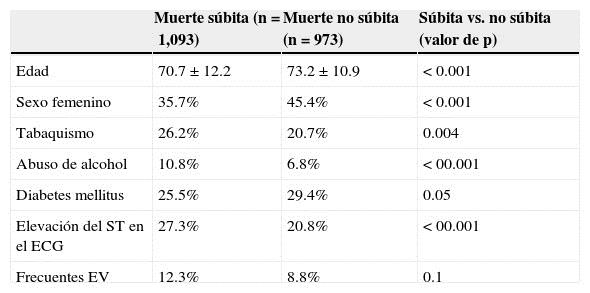

La presencia de isquemia miocárdica sintomática o asintomática es el factor de riesgo más importante para desarrollar muerte súbita en los adultos, desafortunadamente en muchos de estos pacientes será el primer y único síntoma5,8,11,23,41. Se han estudiado pacientes con cardiopatía isquémica crónica y se han detectado algunos predictores de muerte súbita; en un estudio de 30,680 pacientes con diagnóstico de cardiopatía isquémica y seguidos por 3.3 años, se observó que tienen mayor prevalencia de muerte súbita los pacientes del sexo masculino, de menor edad (70 frente a 74 años), fumadores, con elevación del segmento ST y con más extrasístoles ventriculares42 (Tabla 3). Otros marcadores de riesgo de muerte súbita son la mayor presencia de isquemia miocárdica residual detectada por tomografía simple con emisión de positrones, en pacientes que ya han sufrido un infarto de miocardio; a mayor isquemia, mayor es la prevalencia de muerte súbita43. A mayor grado de fibrosis miocárdica detectada por resonancia magnética nuclear, mayor la posibilidad de arritmias ventriculares y muerte súbita38. También se ha demostrado que a mayor prevalencia de oclusión total de arterias coronarias relacionadas con el infarto, mayor la probabilidad de arritmias ventriculares y muerte súbita44.

Tabla 3 Factores de riesgo en pacientes con cardiopatía isquémica que fallecieron por muerte súbita comparados con los que fallecieron de forma no súbita

ECG: electrocardiograma; EV: eventos vasculares.

Modificada de Every et al. 42.